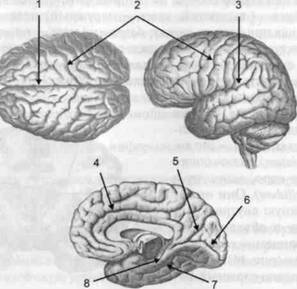

Рис. 13. Латеральная (А), медиальная (Б), конвекситальная (В) и базальная (Г) поверхности больших полушарий

смотрении поверхности мозга и для локализации отдельных участков в нейропсихологии принято пользоваться специальной терминологией, обозначающей плоскость или сектор обзора, на которых фиксируется внимание. Кон-векситальный (букв. — выпуклый, здесь — наружный) мозг — поверхность полушарий, видная при-взгляде сверху; базальный мозг — поверхность и анатомические структуры, видные при взгляде снизу; латеральный мозг — поверхности, видные при взгляде сбоку; медиальный мозг— поверхности полушарий, обращенные внутрь продольной щели мозга (рис. 13).